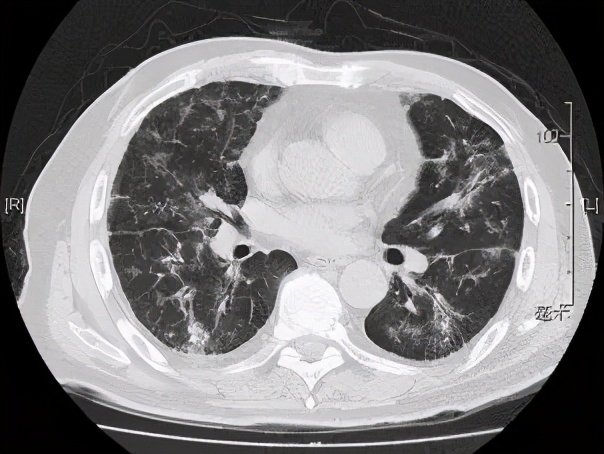

本院胸部CT(2019-08-30)示: 双肺弥漫性间质性改变,有网格状改变、毛玻璃影、局部有支气管牵拉形成支气管扩张的表现。

患者于2019年9月24日到我院随访,活动后气促的症状已得到明显改善,胸部CT示双肺间质性炎症灶较前也有明显好转,查动脉血气示PaO2:81mmHg,PaCO2:38mmHg,相较于9月2日的PaO2:65-68mmHg有明显提升。